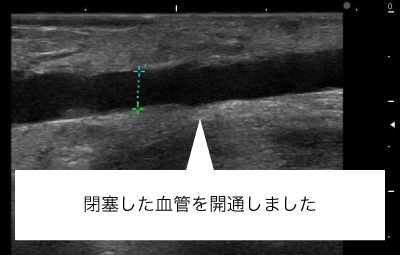

シャント閉塞はしなくても、血流がほとんどないシャント血管部分を長期間放置すると血管内が線維化し部分的に血管が閉塞することがあります。10cm未満のCTOであれば、閉塞した血管の血流を再開させることも可能です。これにより、穿刺部位を広げることが可能となります。